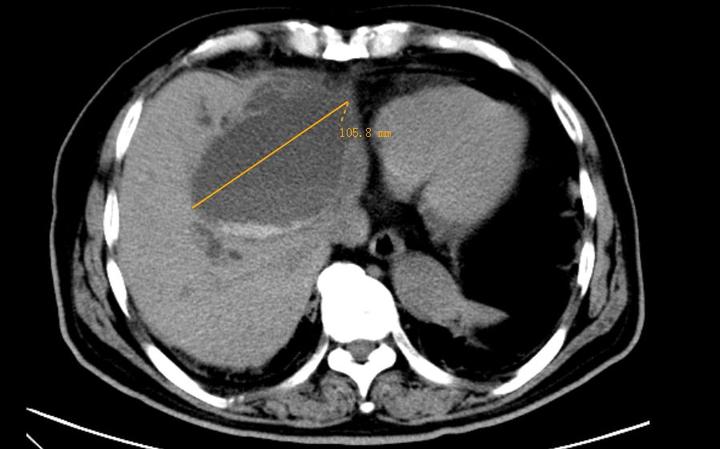

今年已88岁高龄的赵老家住鄞州区咸祥镇,近日因为腹痛伴40℃高烧不退到鄞州二院普外科就诊。经过CT检查,接诊的沙洪存主任发现赵老的左肝的胆管直径已经扩张到10厘米多,足有鸵鸟蛋那么大,占据了肝脏的1/3位置,是正常人的30多倍!更让医生惊讶的是,赵老扩张的胆管内密密麻麻充满了结石,数量之多前所未见,而且远端胆汁已经淤积。